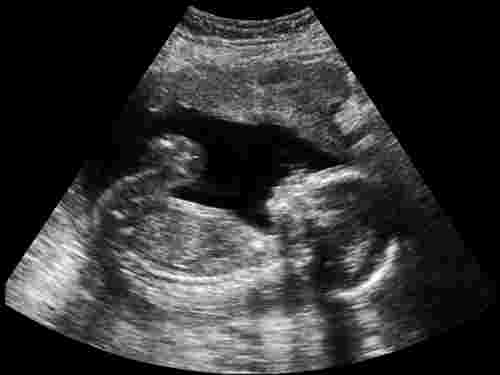

OSCAR, or 'One-stop Clinic for Assessment of Risk for Fetal Anomalies', is a test carried out in the first trimester to screen for the risk of fetal anomalies, in particular Down's Syndrome (Trisomy 21). The test is optional and is available at all hospitals. It involves a Nuchal Translucency (NT) scan and a blood test. If you wish to have an OSCAR test done, your doctor will schedule it usually between the 11th to 14th week of your pregnancy.